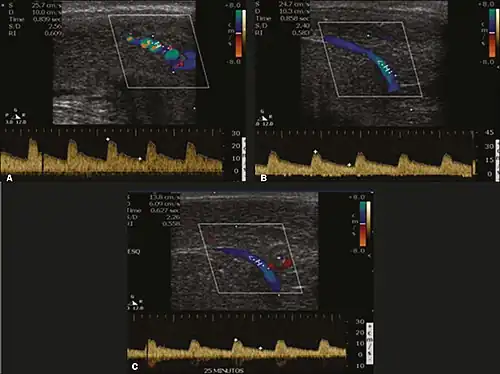

Erection can be induced by injecting 10–20 μg of prostaglandin E1, with evaluations of the arterial flow every five minutes for 25–30 min (see image). The use of prostaglandin E1 is contraindicated in patients with predisposition to priapism (e.g., those with sickle cell anemia), anatomical deformity of the penis, or penile implants. Phentolamine (2 mg) is often added. Visual and tactile stimulation produces better results. Some authors recommend the use of sildenafil by mouth to replace the injectable drugs in cases of contraindications, although the efficacy of such medication is controversial.[48]

Before the injection of the chosen drug, the flow pattern is monophasic, with low systolic velocities and an absence of diastolic flow. After injection, systolic and diastolic peak velocities should increase, decreasing progressively with vein occlusion and becoming negative when the penis becomes rigid (see image below). The reference values vary across studies, ranging from > 25 cm/s to > 35 cm/s. Values above 35 cm/s indicate the absence of arterial disease, values below 25 cm/s indicate arterial insufficiency, and values of 25–35 cm/s are indeterminate because they are less specific (see image below). The data obtained should be correlated with the degree of erection observed. If the peak systolic velocities are normal, the final diastolic velocities should be evaluated, those above 5 cm/s being associated with venogenic ED.[48]

Graphs representing the color Doppler spectrum of the flow pattern of the cavernous arteries during the erection phases. A: Single-phase flow with minimal or absent diastole when the penis is flaccid. B: Increased systolic flow and reverse diastole 25 min after injection of prostaglandin.[48] -

Longitudinal, ventral ultrasound of the penis, with pulsed mode and color Doppler. Flow of the cavernous arteries at 5, 15, and 25 min after prostaglandin injection (A, B, and C, respectively). The cavernous artery flow remains below the expected levels (at least 25–35 cm/s), which indicates ED due to arterial insufficiency.[48]